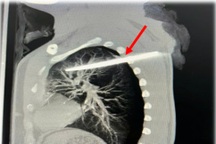

Sau khi thăm khám và thực hiện các xét nghiệm cấp cứu, bao gồm chụp cắt lớp vi tính 32 lát cắt, các bác sĩ xác định có dị vật tại đoạn C3-C5 với kích thước 5x3cm, có móc thép.

Bệnh nhân sau đó được chuyển vào Khoa Gây mê - Hồi sức. Với sự phối hợp nhịp nhàng của đội ngũ y bác sĩ, ca phẫu thuật nội soi ống cứng đã diễn ra thành công, lấy ra dị vật là cung răng giả sắc nhọn.

Ca nội soi kéo dài khoảng 40 phút, dị vật được lấy ra có kích thước 3x5cm. Do cấu tạo của hàm răng giả có nhiều mấu, nó bám chặt vào thực quản, gây khó khăn hơn so với các dị vật thông thường khác.